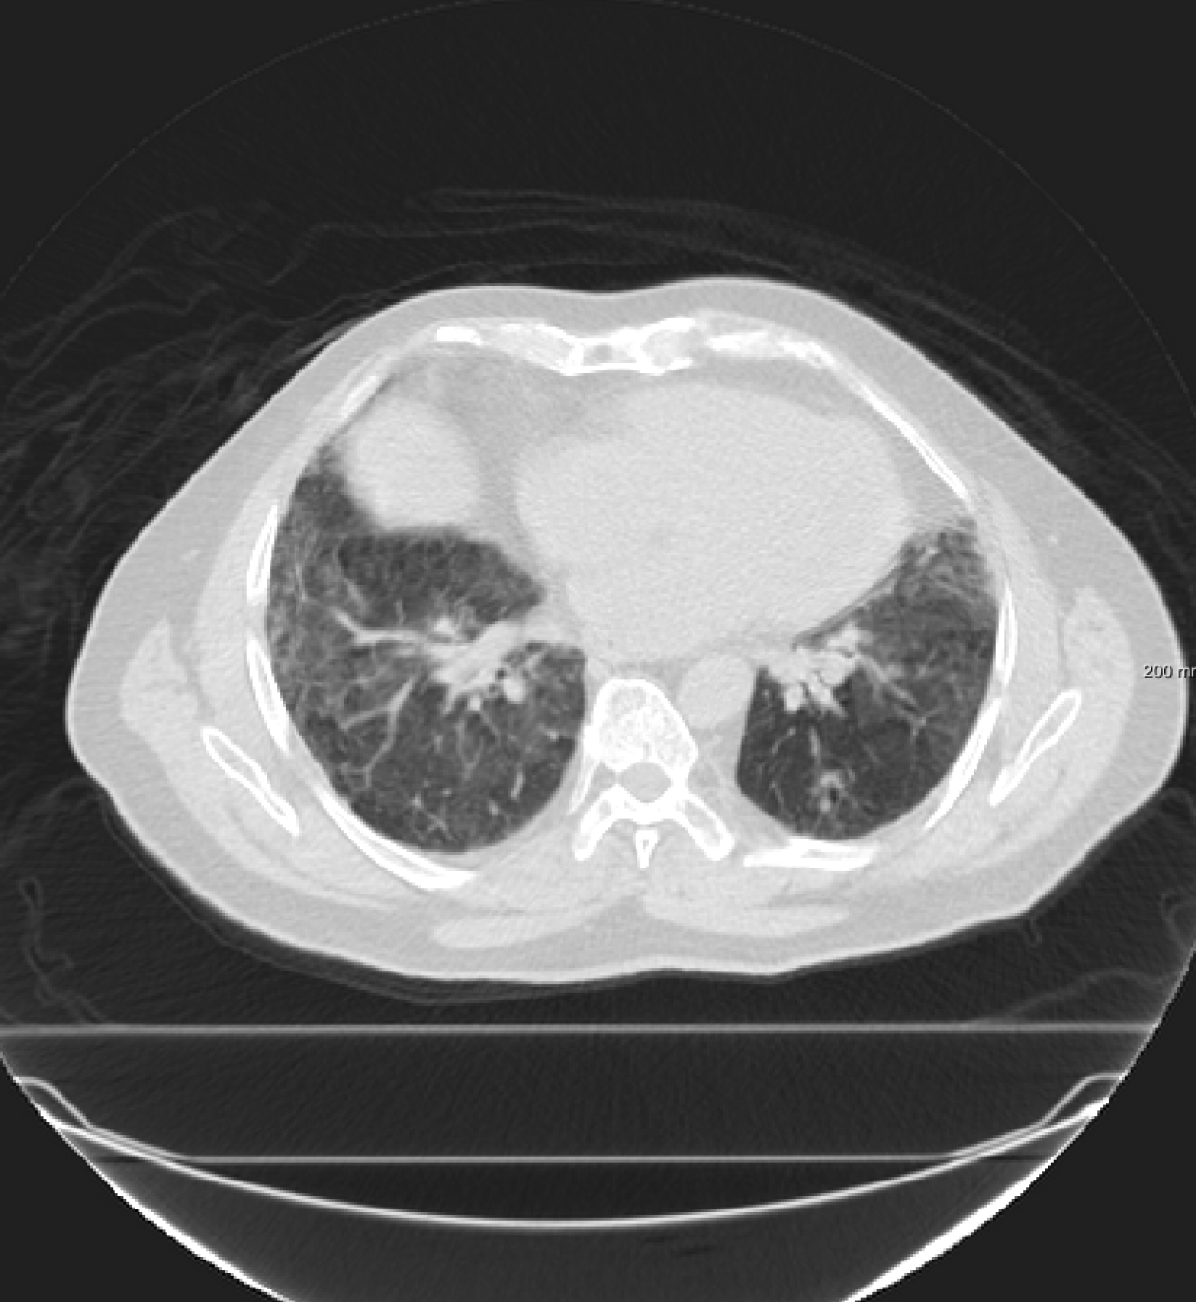

Three chest CT scan datasets are used in this study: The SPREAD (Stolk et al., 2007), the DIR-Lab-4DCT (Castillo et al., 2009) and the DIR-Lab-COPDgene dataset (Castillo et al., 2013).

In the SPREAD database, 21 pairs of 3D chest CT images are available with a baseline and a follow-up image in each pair. The follow-up images are taken after 30 months. Both images are acquired in the inhale phase. Patients in this study are aged between 49 and 78 years old. The size of the images is approximately with a mean voxel size of mm. About 100 well-distributed corresponding landmarks were previously selected (Staring et al., 2014) semi-automatically on distinctive locations (Murphy et al., 2011). Two cases (12 and 19) are excluded because of the high uncertainty in the landmarks annotation (Staring et al., 2014).

For the DIR-Lab-4DCT database, a comparison between RegNet and affine, B-spline (three resolutions), an advanced conventional registration method using sliding motion (Berendsen et al., 2014) and three other CNN-based methods (Eppenhof and Pluim, 2018; de Vos et al., 2019; Sentker et al., 2018) is available in Table IV. It can be seen that training with “S+M” improved performance slightly with respect to just “S”. Adding the respiratory motion category improved performance substantially, as these are inhale-exhale pairs; this is predominantly caused by the patients where the TRE after affine registration was still quite large. An example visualization is also available in Fig. 5(f), showing that adding the respiratory motion category can align images better in the diaphragm region. The advanced conventional registration method that leverages sliding motion (Berendsen et al., 2014) is still better than RegNet. Note that RegNet was not trained on the DIR-Lab-4DCT data, similar to Eppenhof and Pluim (2018); Sentker et al. (2018). However, de Vos et al. (2019) and Eppenhof and Pluim (2018)-DIR methods were trained on the same database but using cross-validation to report the results. Also note that the results reported in Sentker et al. (2018) are averaged over all phases of DIR-Lab-4DCT (T00 to T10), while the results of other CNN methods (including RegNet) are reported between the maximum inhale and maximum exhale phase (T00 and T50). These reported results are therefore likely somewhat better than the results for T00 and T50 only.